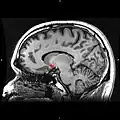

Sagittal MRI slice with highlighting (red) indicating the nucleus accumbens

Nucleus accumbens highlighted in green on sagittal T1 MRI images